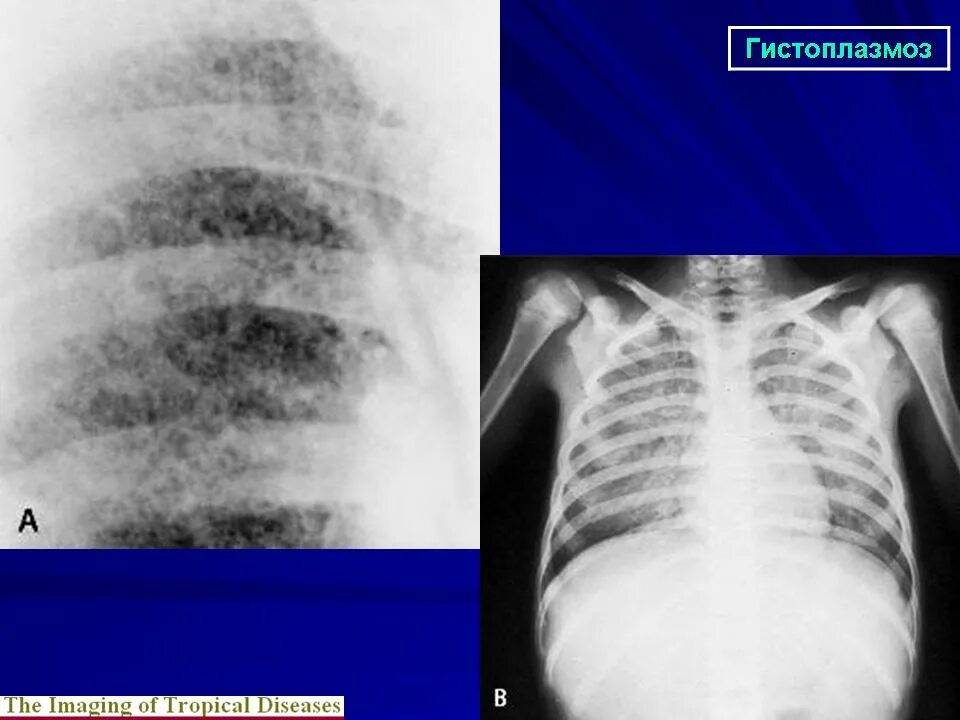

Гистоплазмоз это